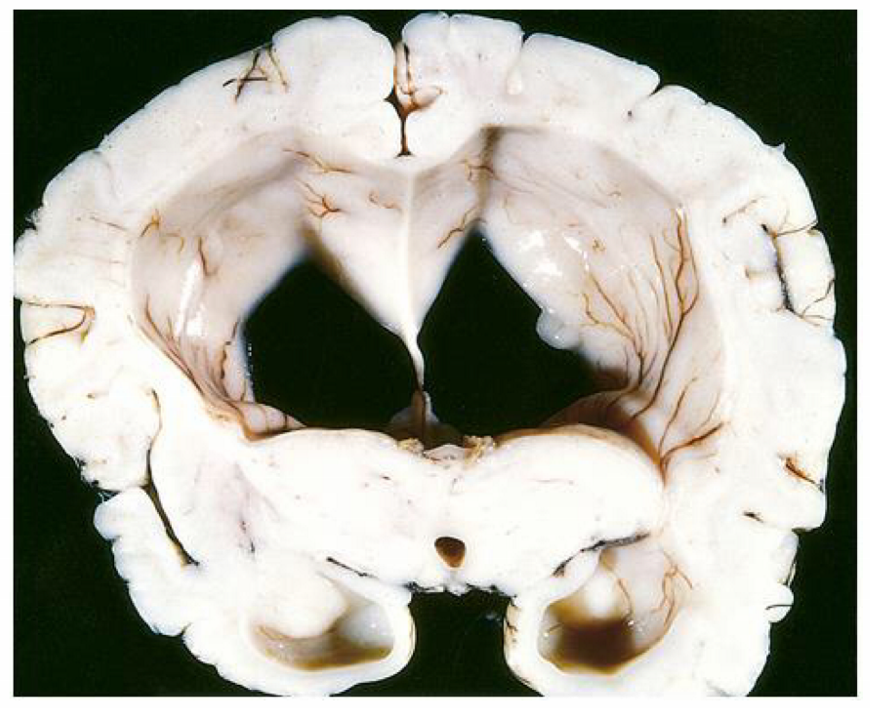

the pathogenesis of the condition seen in the image arises from defective ___ of \_\_\_\_

the pathogenesis of the condition seen in the image arises from **defective cleavage** of **transmembrane cellular proteins**

on histology of the condition seen in the image, ____ proteins accumulate intracellularly, while ____ accumulate extracellularly

on histology of the condition seen in the image, **Tau proteins (neurofibrillary tangles)** accumulate intracellularly, while **A-B amyloid plaque** accumulate extracellularly

describe the presentation of the condition seen in the image

**slowly progressive dementia** (impaired cognition) but motor & sensory intact **start with short-term memory loss** (temporal) → paralysis & bed-ridden (frontal & parietal)

on CT scan of the condition seen in the image, there is flattening of ___ with enlarged \_\_\_\_

on CT scan of the condition seen in the image, there is **flattening of sulci & gyri** with **enlarged ventricles**

the most common cause of death in the condition seen in the image is \_\_\_\_

the most common cause of death in the condition seen in the image is **aspiration pneumonia**

describe how a complication of the condition seen in the image is lobar hemorrhages

**cerebral amyloid angiopathy** = deposition of amyloid in the walls of cerebral vessels